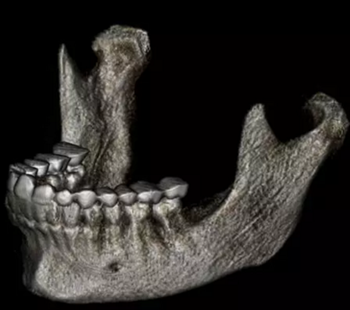

在輸出的3D模型上,使用體內軟件(Anatomage,San Jose,Calif)將下頜骨以最小的間隔從顱骨上分離(圖5)用于保留下頜骨的咬合細節(jié),游離的下頜骨被保存(圖6,A)。同時,將沒有下頜骨的顱骨導出并保存(圖6,B)。

圖6. A,從整個3D模型上修剪的下頜骨; B,修剪的顱骨。